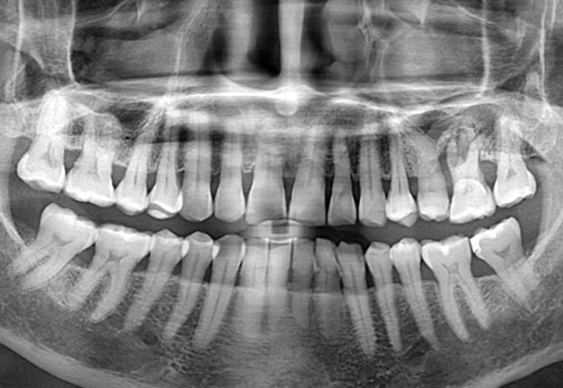

상악동 측방 거상술.

After

위 케이스는 이미 상악의 잇몸 뼈가 많이 부족하여

상악동 거상술을 시행하여 뼈이식을 충분히 시행한 후

임플란트 식립을 통해 보철을 완료하였습니다.